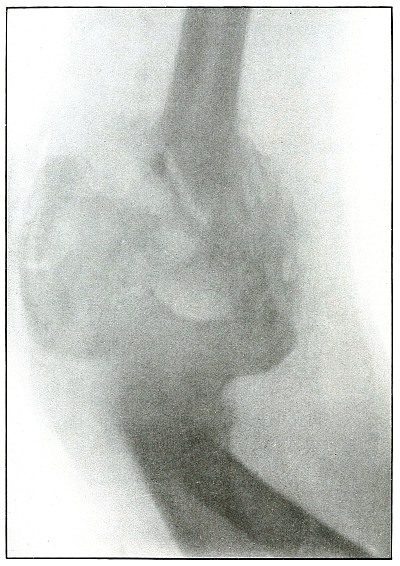

Rifle—Plate 17.

UPPER EXTREMITY.

Gunshot Fracture of the Elbow.

The bullet in transverse course and high velocity through both bones of the forearm struck the head of the radius, thus starting several splitting lines of fracture and separating large fragments. Smaller fragments which received some of the energy of the missile have been carried along with it in turn, striking the ulna and carrying away smaller fragments from it and causing the laceration which marks the wound of exit.

Such wounds, with laceration of soft parts and fragmentation of the bone, are prone to infection, against which treatment is directed. The indications to be met are much like those of the wound shown in plates 18 and 19. Excision or immediate methods of bone repair are contraindicated by infection.

Results will depend upon the nature and extent of infection. [Pg 46]